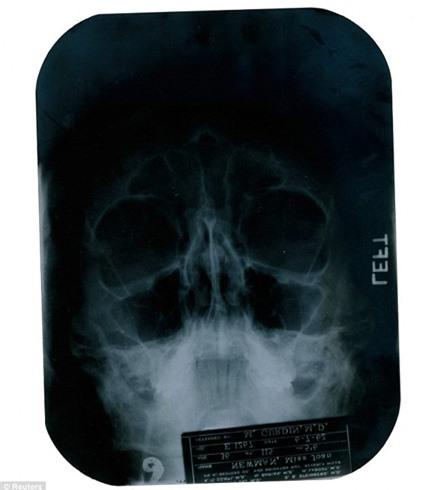

Phim chụp X-quang được ghi chú vào ngày 6/7/1962 sau khi Marilyn Monroe gặp gỡ bác sĩ Gurdin hai tháng trước khi ngôi sao bạc mệnh qua đời ở tuổi 36 vì sử dụng thuốc quá liều. Cơ quan chức năng kết luận, Marilyn Monroe chết vì tự vẫn. Biểu tượng sắc đẹp còn bị hãng phim 20th Century Fox sa thải dù bộ phim Something's Got to Give vẫn chưa hoàn tất do thường xuyên vắng mặt tại phim trường.

Ngoài bức phim chụp xương cằm của Marilyn Monroe, một bức phim X-quang khá chụp phần ngực của ngôi sao nổi tiếng cũng từng được mang bán đấu giá vào năm 2010 và được bán với giá 45 nghìn USD.